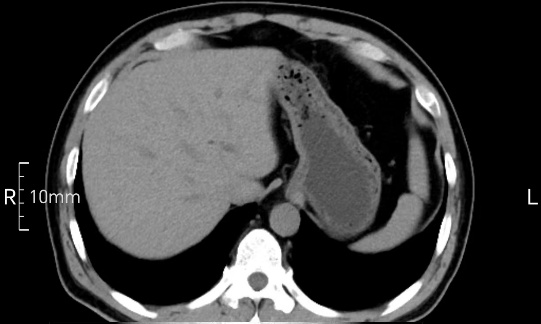

看看下面三幅便知遵醫(yī)囑的重要性。

完美禁食且喝飽飽,胃壁完美展現(xiàn)。

CT檢查前的“禁食”和“喝飽”,看似矛盾,實則合情合理,分工合作:空腹:是為了讓上腹部(肝膽胰脾腎等)的圖像清晰無干擾,并保障檢查安全。喝水:有效的充盈胃部和、腸道使圖像清晰呈現(xiàn)。兩者巧妙配合,都是為了給您一個最精準的診斷結果。